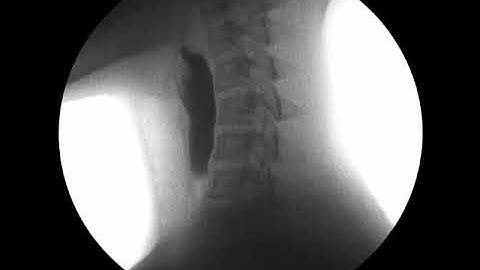

Swallow Study Using DynaVue